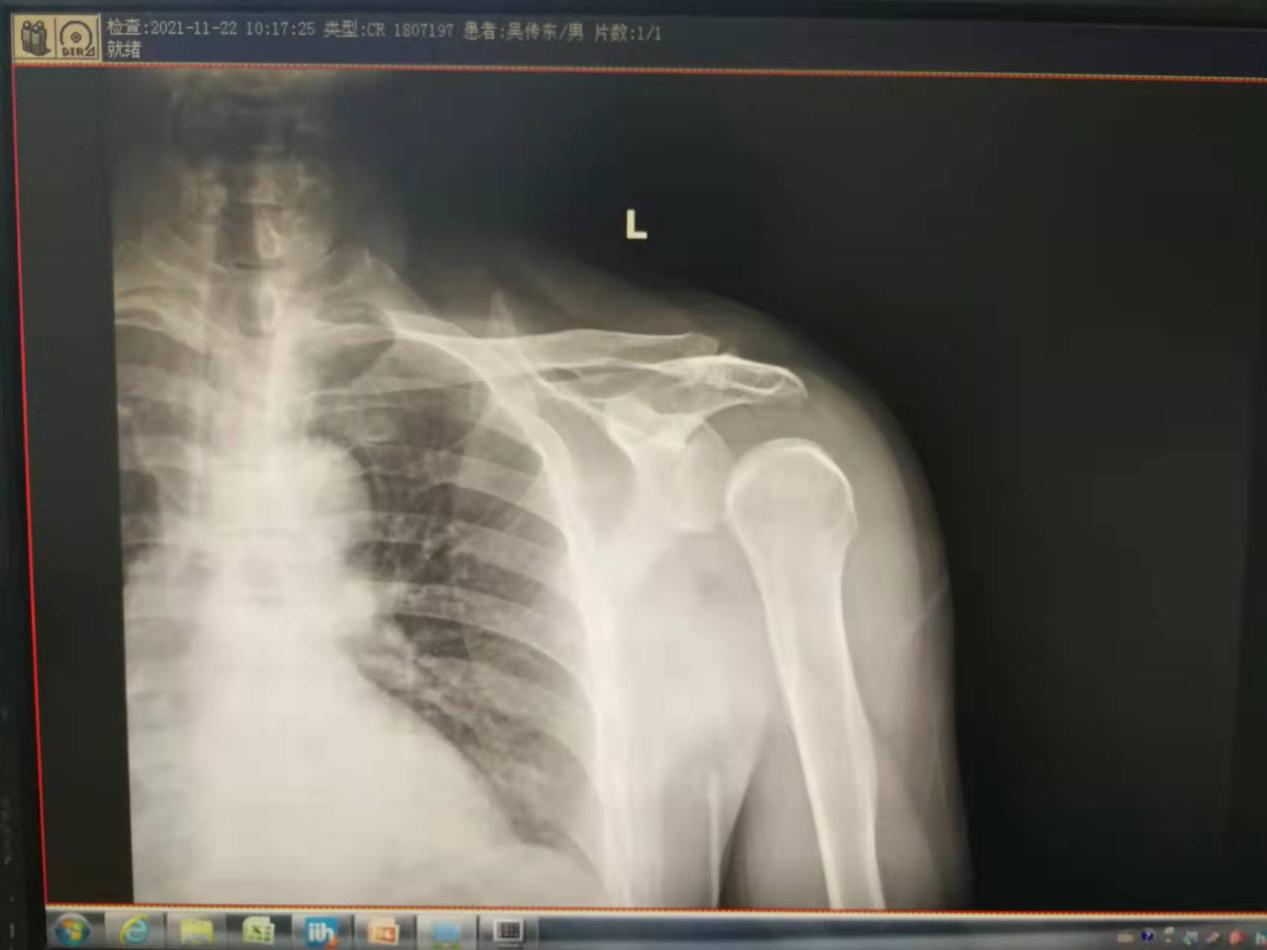

吴某,男性,62岁,车祸后左肩部疼痛、活动部分受限2小时。入院前查体,左肩关节未见明显方肩畸形,左肩关节正位片显示没有脱位,按压关节盂无明显空虚感,无明显弹性固定感,内旋未见明显受限,外旋受限,指端感觉活动血运正常。

但是患者肩关节仍疼痛明显,入住兰陵县人民医院后,医生给予重新拍左肩关节正位片,症状比入院前明显了,“灯泡征”出现了,显示后脱位;经过CT/MRI的进一步证实,确定是后脱位。